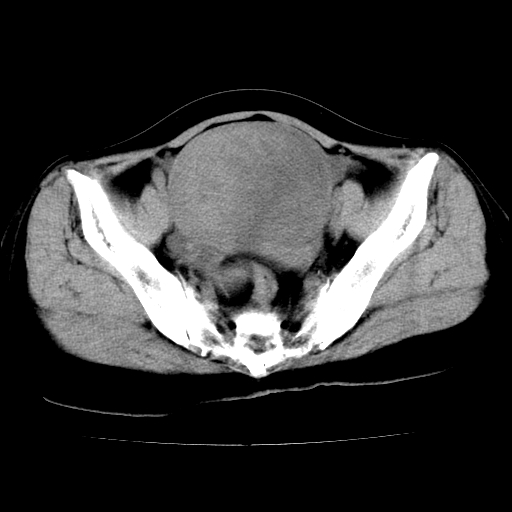

标题: CT24785:女,62岁,发现下腹部肿物半年。 [打印本页]

女,62岁,发现下腹部肿物半年,下腹部不适。

卵巢囊腺瘤或囊腺癌可能。

考虑附件粘液性囊腺瘤可能性大。

考虑附件囊腺癌。